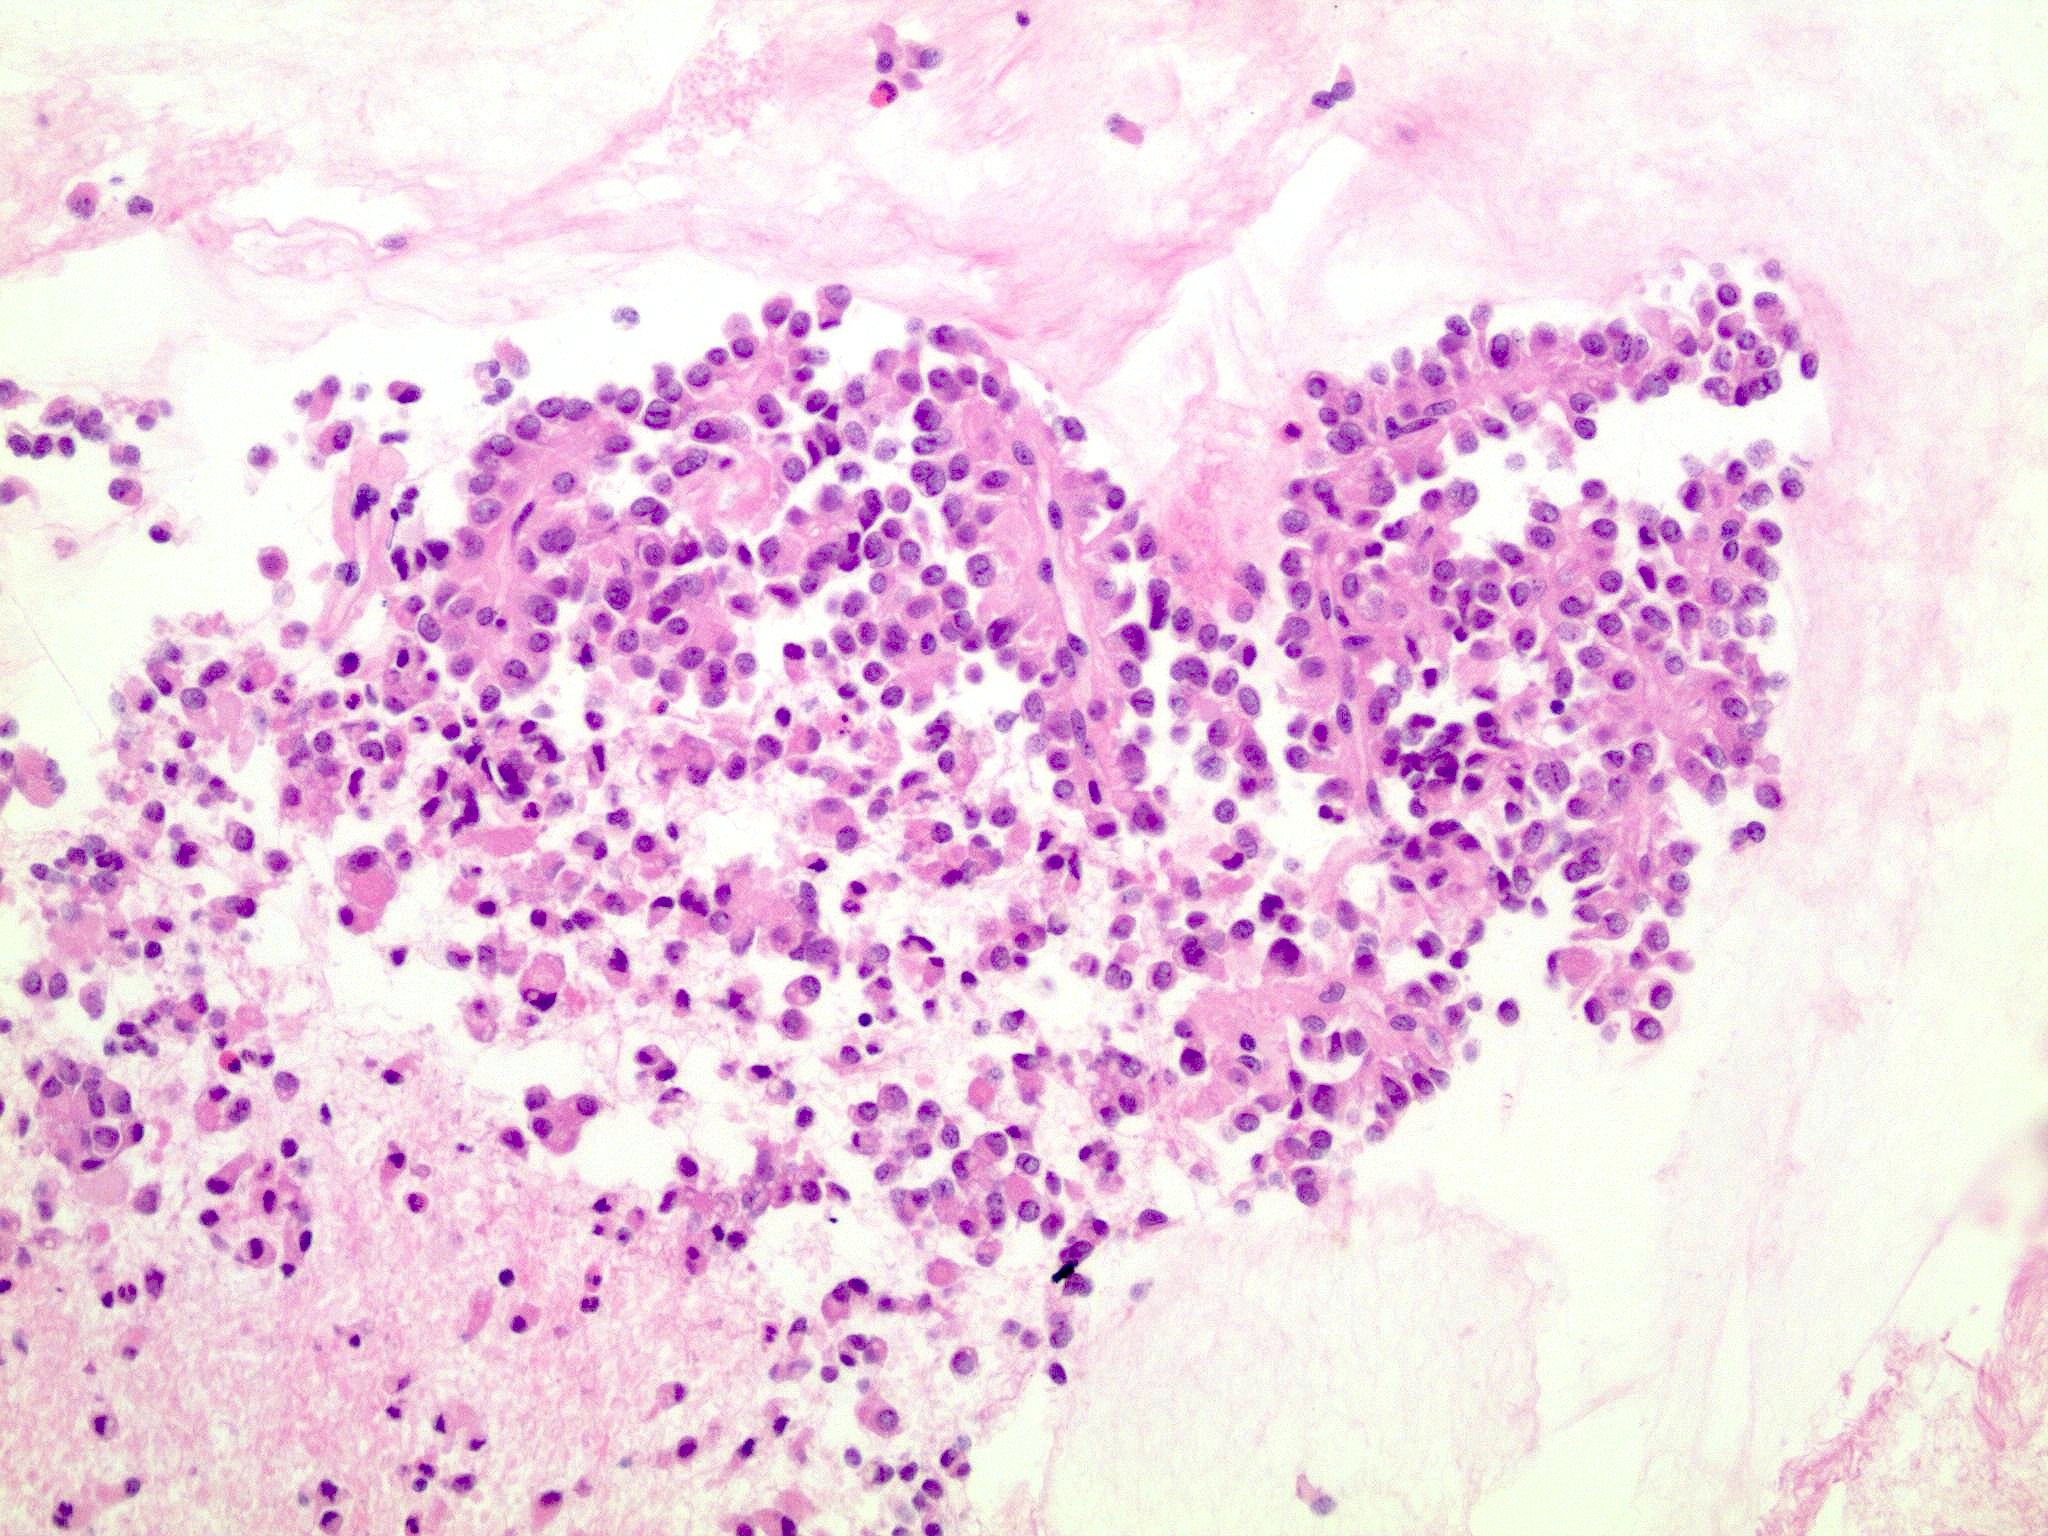

Microscopic (histologic) description

- Tumors are heterogeneous, with variable admixture of solid and pseudopapillary areas

- Solid areas are comprised of uniform cells admixed with capillary sized blood vessels

- Pseudopapillae are formed due to tumor cells getting detached from blood vessels forming fibrovascular stalks or rosette-like structures (Arch Pathol Lab Med 2020;144:829)

- Stroma usually shows various degrees of hyalinization or evidence of degeneration, such as hemorrhage, foamy macrophages, calcification and cholesterol clefts

- Tumor cells usually have a moderate amount of eosinophilic cytoplasm with intracytoplasmic hyaline globules (PAS+ and diastase resistant, positive for alpha-1-antitrypsin) and perinuclear vacuoles (Am J Surg Pathol 2011;35:981)

- Relatively uniform nuclei with finely textured chromatin, inconspicuous nucleoli and characteristic longitudinal grooves

- Variants include clear cell, oncocytic and pleomorphic

- Rare mitotic figures

- Although grossly well circumscribed, microscopic finding of infiltration to the surrounding pancreatic tissue is not uncommon

- Rare cases of highly aggressive behavior; histological features in those cases included diffuse growth pattern, extensive necrosis, significant nuclear atypia, high mitotic count (35 - 70/50 high power fields) or sarcomatoid features (Am J Surg Pathol 2005;29:512)

Microscopic (histologic) images

Contributed by Monika Vyas, M.D., Omid Savari, M.D. and Raul S. Gonzalez, M.D.